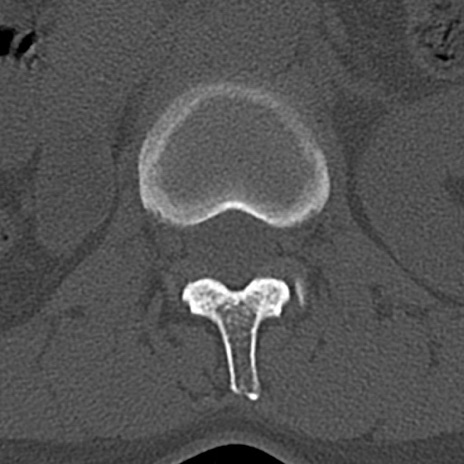

腰椎CT

横断像と矢状断像